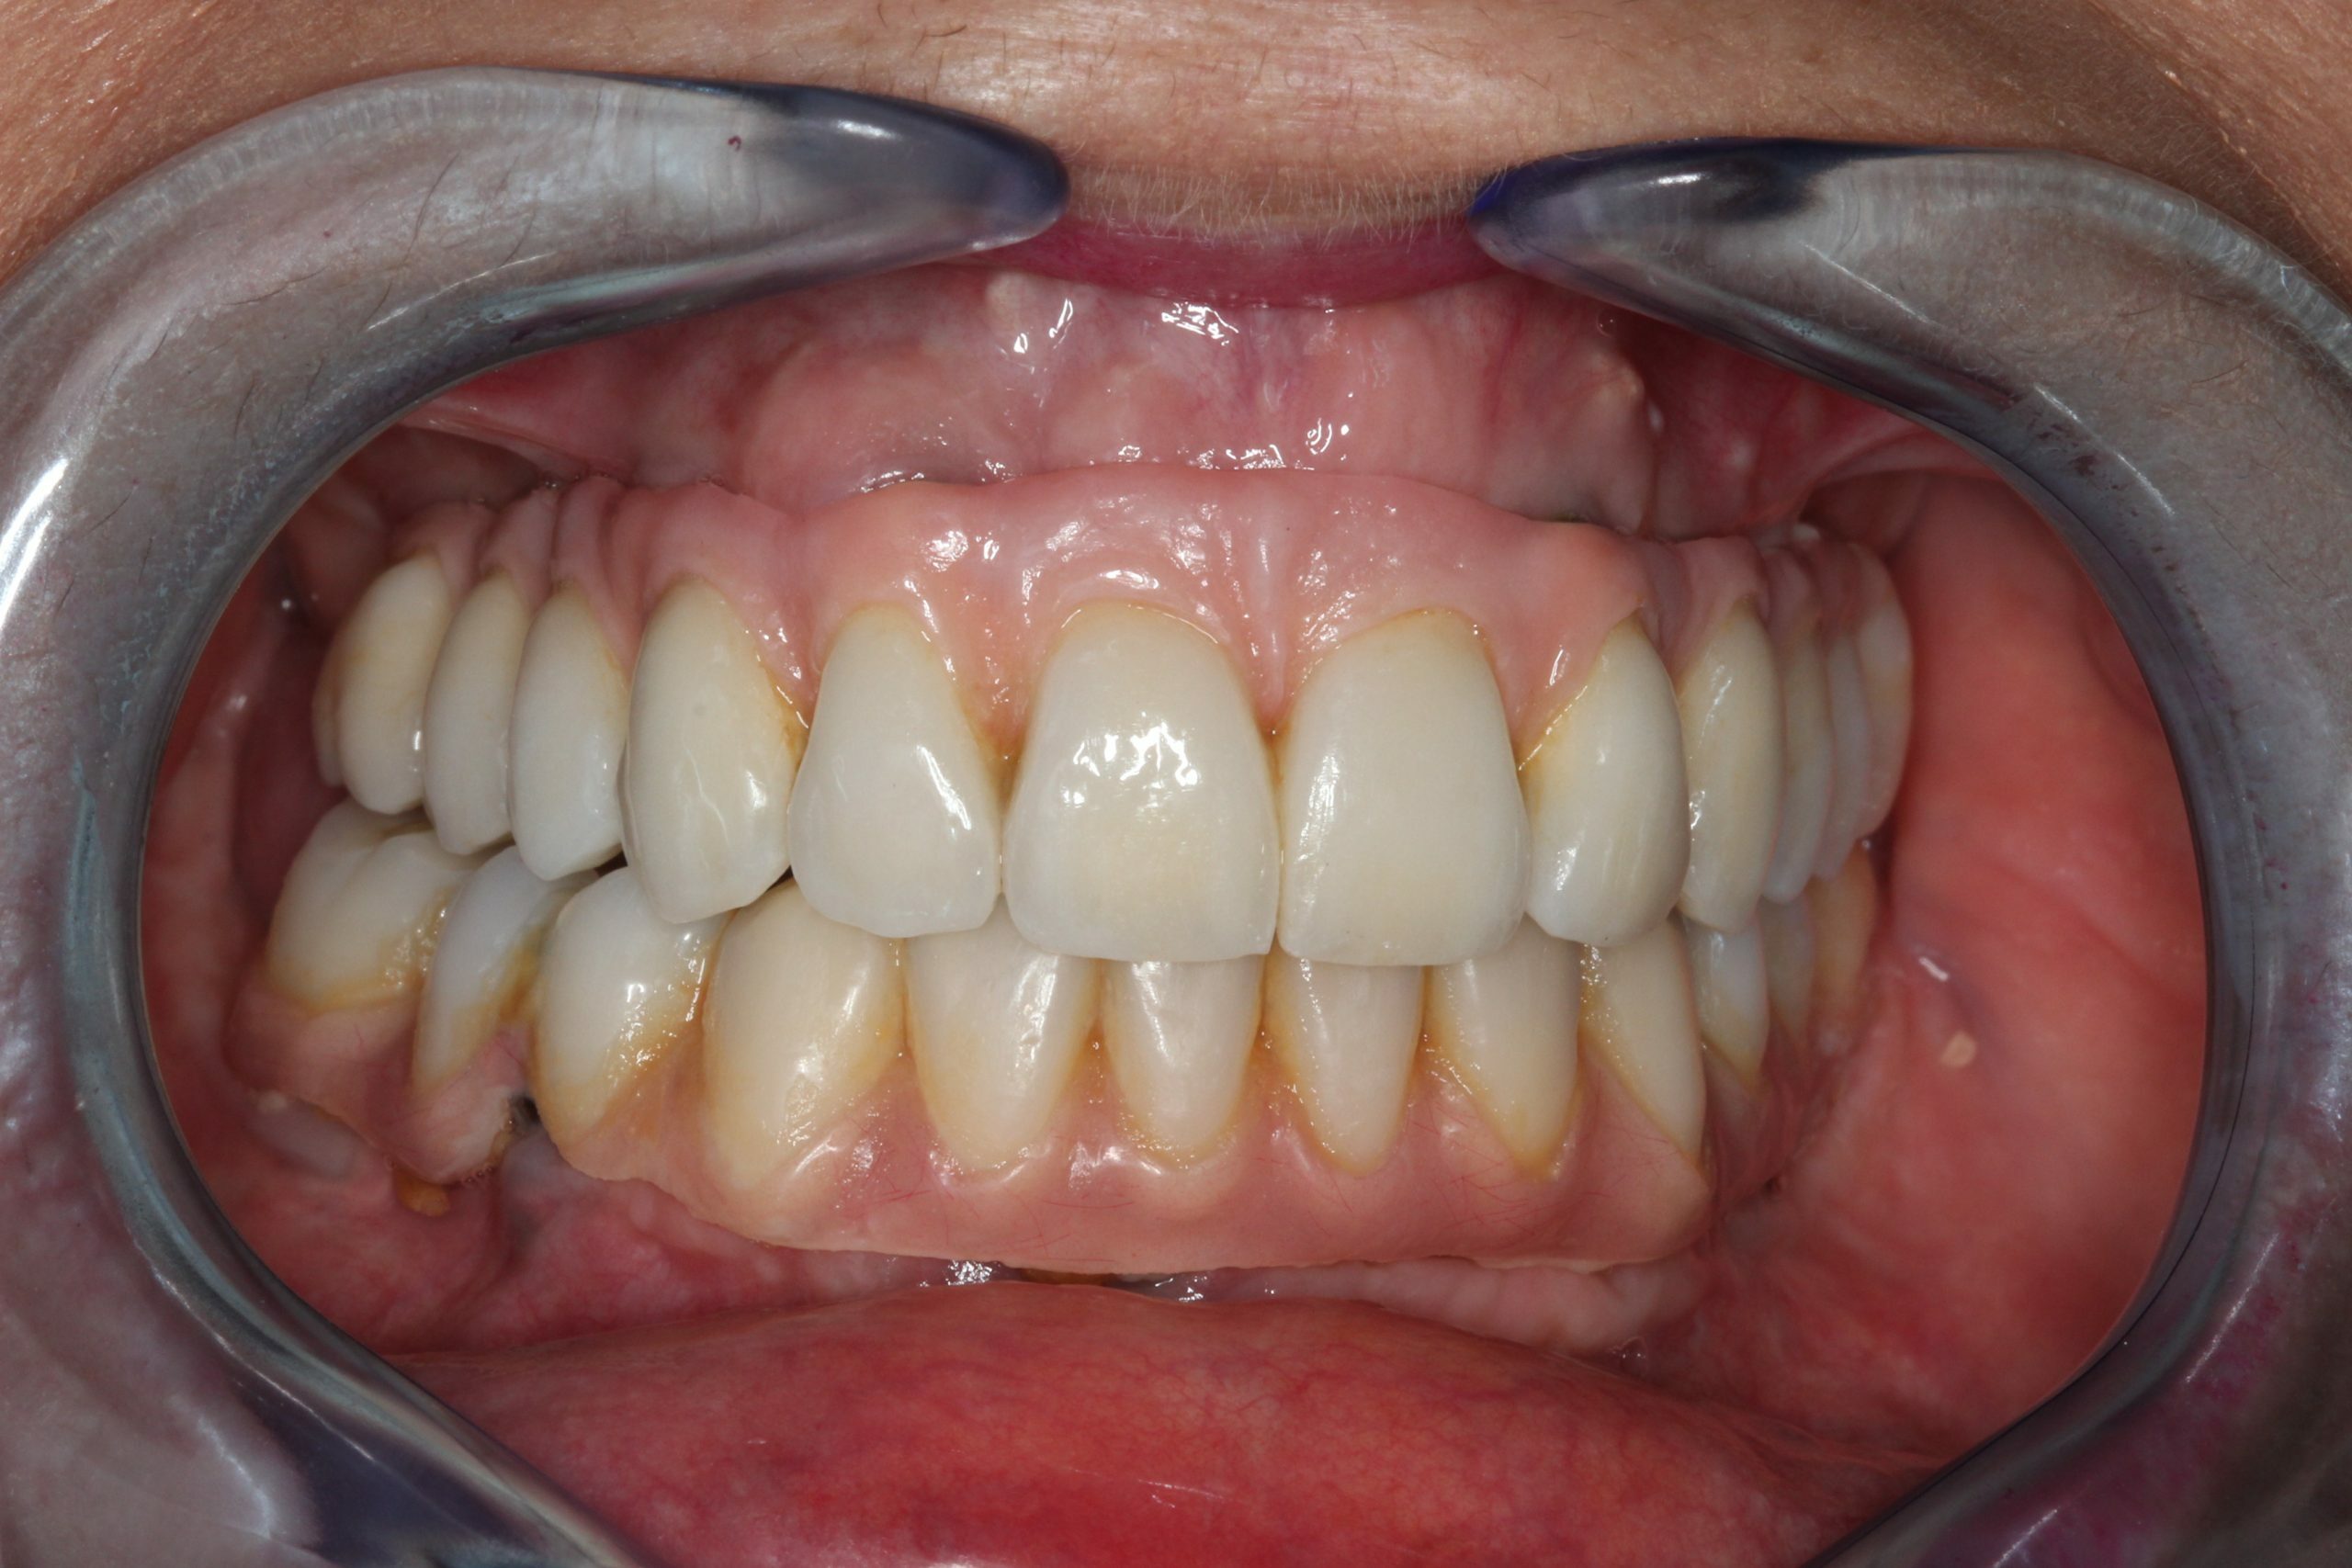

Casos de Éxito: Experiencia que Genera Confianza

Nuestra experiencia se centra en la implantología compleja y la regeneración ósea, logrando rehabilitaciones dentales estables y duraderas con el máximo rigor médico.